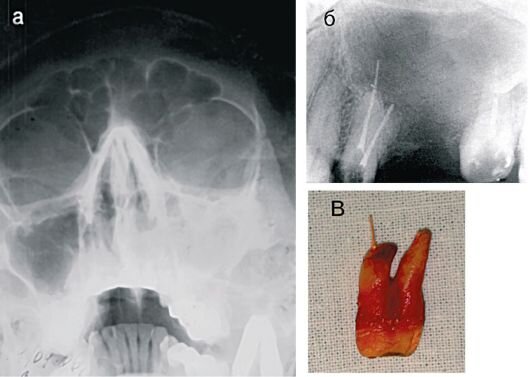

Один китаец по имени Чжан Биньшэн, из города Харбин, совершенно ничего не подозревая, умудрился 20 лет прожить с зубом вносу. Лишь недавно ему посчастливилось обратиться к врачам с жалобами на длительную заложенность носа и тяжесть в дыхании. Незадачливому китайцу медики сделали рентген носовой полости и к всеобщему удивлению обнаружили странный сгусток, который был очень похож на человеческий зуб. Как оказалось, еще в 1999 году, когда Чжану было всего 10 лет, он выпал из окна магазина. Падал он с третьего этажа. Последствием этого падения стало сотрясение мозга и два выбитых зуба. Как смогли предположить врачи, видимо при падении один из зубов сместился в носовую полость и там прижился. Тело Чжана решило не отвергать переместившийся зуб, и поэтому он столь длительное время оставался не замеченным. Хирургам ничего не оставалось делать, как провести операционное вмешательство по удалению зуба. Операция длилась всего полчаса и прошла недолго, сантиметровый зуб был удален, а Чжан благопо

Один китаец по имени Чжан Биньшэн, из города Харбин, совершенно ничего не подозревая, умудрился 20 лет прожить с зубом вносу. Лишь недавно ему посчастливилось обратиться к врачам с жалобами на длительную заложенность носа и тяжесть в дыхании. Незадачливому китайцу медики сделали рентген носовой полости и к всеобщему удивлению обнаружили странный сгусток, который был очень похож на человеческий зуб.

Как оказалось, еще в 1999 году, когда Чжану было всего 10 лет, он выпал из окна магазина. Падал он с третьего этажа. Последствием этого падения стало сотрясение мозга и два выбитых зуба. Как смогли предположить врачи, видимо при падении один из зубов сместился в носовую полость и там прижился.

Тело Чжана решило не отвергать переместившийся зуб, и поэтому он столь длительное время оставался не замеченным. Хирургам ничего не оставалось делать, как провести операционное вмешательство по удалению зуба. Операция длилась всего полчаса и прошла недолго, сантиметровый зуб был удален, а Чжан благополучно шел на поправку.